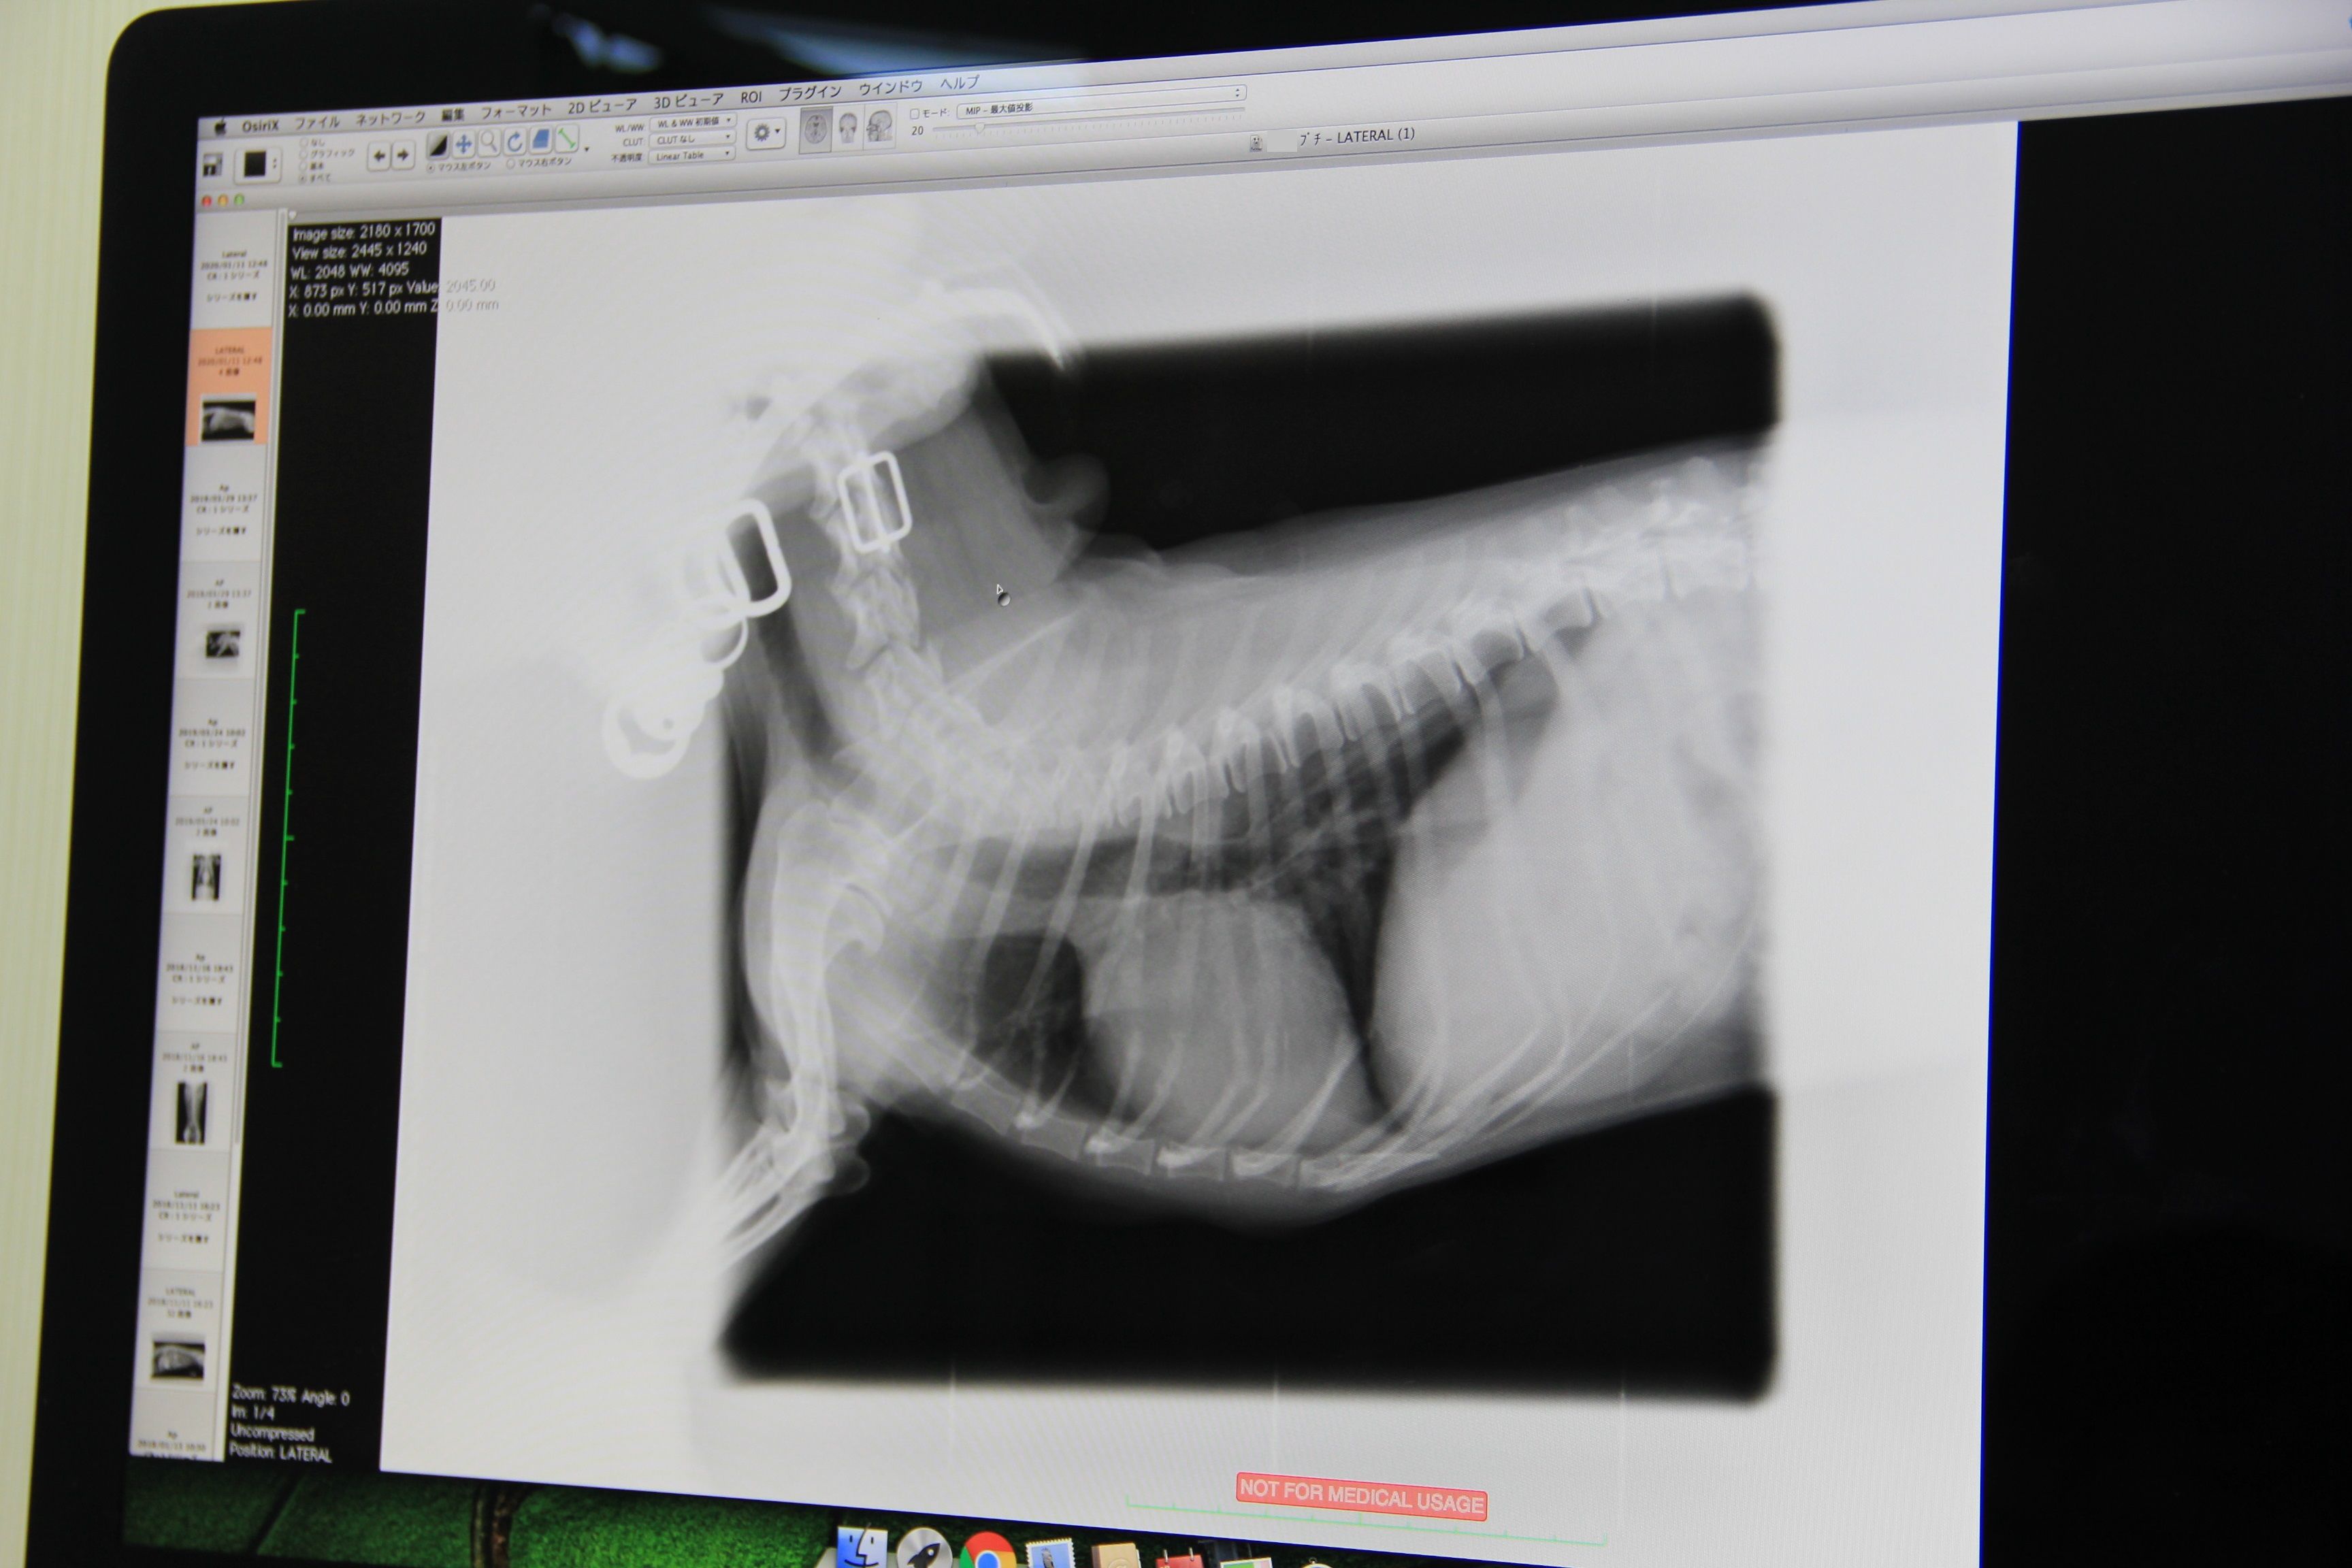

気になることがあって病院で診察だ ▼・。・▼… 2025年10月19日